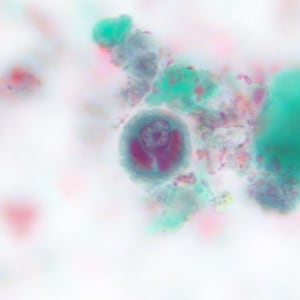

Case #228 – May, 2008

Within a week of returning from a conference in Mexico, a 28-year-old woman presented to her primary care physician with cramps, abdominal pain, gas and diarrhea. A routine Ova and Parasite (O&P) examination was performed on stool specimens. Figures A–F show objects observed on a trichrome-stained slide prepared from the stool. All images were taken at 1000x oil magnification. The objects in Figures A–C measured 12 micrometers. The objects in Figures D and E averaged 10 micrometers. The object in Figure F measured 12 micrometers in diameter. What is your diagnosis? Based on what criteria?

Figure A